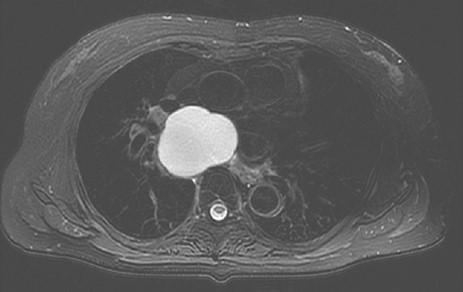

An 83-year-old-woman presented with a subcarinal mass detected by a precise examination of upper abdominal pain worsening after meals. Magnetic resonance imaging revealed a well-circumscribed cystic mass in the subcarinal area compressing the surrounding organs and suggested a BC as the most likely diagnosis (Fig 1). She had poorly controlled type 2 diabetes mellitus (A1c level 9.1%), hypertension, and also noted worsening paroxysmal atrial fibrillation (CHADS2 score3) and was receiving dabigatran etexilate over the last several months. A surgical resection of the cyst was recommended. With the patient in the prone position, two 5-mm ports in the third and fifth inter costal spaces (ICSs) and a 12-mm port in in the seventh ICS on the mid-axillary line were made, respectively. An additional 5-mm port was inserted into the eighth ICS on the scapular line and used as a camera port (Fig 2). Carbon dioxide (CO2) was insufflated at a pressure of 8–mm Hg and then a tense mass was clearly visualized in the subcarinal area (Fig 3). The cyst wall was found to have strictly adhered to the adjacent organs suggestive of past inflammatory events. Because an attempt to dissect between the cyst and lung resulted in parenchymal injury with alveolar leakage, we considered that the lesion was not amenable to a complete excision. After

T2 weighted image showing a subcarinal cyst compressing the surrounding organs.